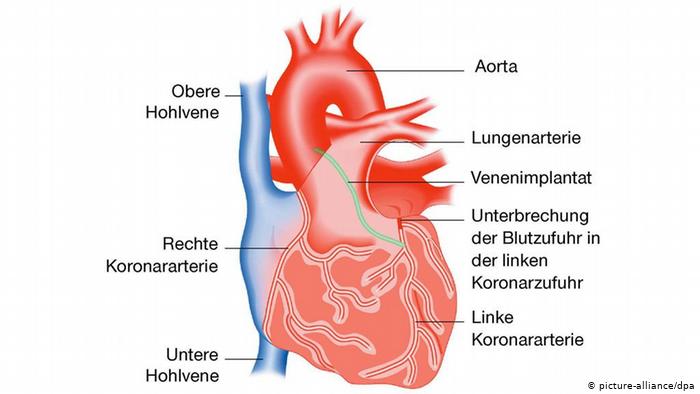

عملية القلب المفتوح

كان الأطباء يرغمون على إيقاف عمل الدورة الدموية في الجسم عند إجراء عملية جراحية في القلب. ولكن في خمسينات القرن الماضي اكتشف الجراحون طريقة جديدة مكنتهم من حل المشكلة عن طريق استعمال جهاز يستخدم مؤقتا إثناء العملية الجراحية ويقوم بتزويد الدم بالأوكسجين ومن ثم إرساله إلى باقي الجسم، وفي هذه الحالة يقوم الجهاز بعمل القلب والرئة معاً.

القسطرة الطبية

الطب الحديث بإمكانه الكشف الكامل عن عمل القلب والتعرف على مشاكله إضافة إلى القيام بتدخلات جراحية دون فتح بطن المريض. حيث يقوم الأطباء باستخدام عملية القسطرة، أي إدخال أنبوب معدني أو مطاطي في جسم الإنسان يتم عن طريقه إدخال أدوات جراحية وطبية وإجراء العملية الجراحية في قلب المريض.